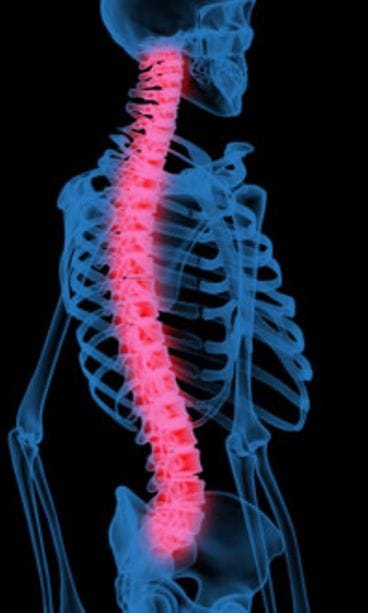

– Siinä vastaanottohuoneessa istuessani katseeni kiinnittyi seinälle ripustettuihin kuviin kumaraisista selkärangoista. Sanoin, että minullahan on ihan tuollainen ryhti, Kristiina kertoo.

Kristiina on lyhentynyt osteoporoosin takia kolme senttimetriä. Jalan hiusmurtuma on kuitenkin parantunut, eikä sairaus juuri aiheuta kipua muualle kuin alalantioon: selkäranka on käyristynyt sen verran, että se painaa luita lysyyn.